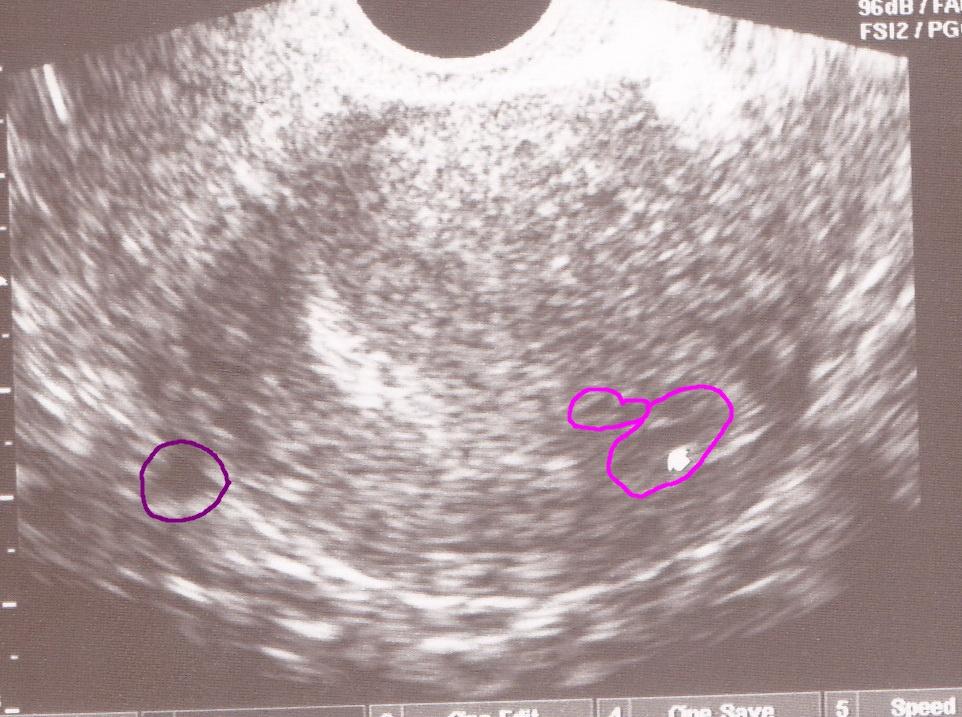

Vidíte na tejto fotke jedno alebo dve bábätka?

Ahojte maminy a cakatelky, prosim vas pekne, zda sa to iba mne alebo vidite na obrazku z UZ viac ako jedno babatko? dve fotky vytvorene tesne po sebe a na prvej vidim vpravo v hornom rohu (akoby za ciernou dutinou) babatko spredu (hlavicka a lava rucicka) a hned na druhej zozadu akoby stavce, hlavicku a svetle "ciarky" - nozicky. Totiz cim viac to pozorujem, tym viac neviem na com som. Podla mna sa pocas "fotenia" otocilo lebo aj to prve sa velmi rychlo stale hybalo. Prosim vidi este niekto okrem mna viac ako jedno dietatko ci nie? dakujem za vase nazory, DAKUJEM velmi velmi!

PS to dietatko ( aj ked vidno iba jeho cast) v strede v tej tmavociernej casti je iste a potvrdene doktorom... ;)

@stratenanajdena mimo maternice ziadne dalsie dieta nie je a ani nemoze byt. Je to hra tienov. Nielen bez maternice - ale bez plodovej vody by sa tvoje dieta nemalo sancu vyvijat. Ta by bola tiez zobrazena ako cierny vak okolo a to tam nie je. Nestresuj sa zbytocne. Lekar take velke babo neprehliadne v dnesnej dobe ani nahodou. To, co tu pisu su xy rokov stare pripady, kedy neboli dnesne ultrazvuky a nemonitorovali srdiecko plodu.

@stratenanajdena to čo je v ramcekoch na tých fotkách dieťa urcite nie je 😉

@stratenanajdena to vyzera na cystu!!! 😲

@bocianka123 mozno ti baby napisu ze vajecnik alebo mocovy mechur. a ja absolutne netusim takze nemam odpoved. No tak to mna by zaujimalo, co je aj toto:

pretoze tam na lavom rohu dole na fotke (inac prava strana brucha) som mala niekolko tyzdnov velmi silne bolesti, zaco som musela aj do nemocnice na kontrolu, ci nie je mimomaternicove, lebo mali podozrenie. Neskutocne bolesti som mala. Bodave, nevydrzatelne tlaky. Dovnutra, do jedneho miesta, niekolko tyzdnov. To som nezazila nikdy predtym. Mne to vo fialovom kruzku pride tak, ze akoby mi to natahovalo tu jazvu po sekcii, ktoru mozno aj na tej mizernej fotke vidite, biele stehy, zastopkana od kraja po kraj :( mozno to mi sposobovalo tie bolesti nech uz to je cysta alebo cokolvek ine.

bud je tam schovane tajomstvo - dalsie babätko, alebo to je veeeelmi pomaly pristroj, ktory cvakol dietatko v pohybe, takze ho vidno na fotke dvakrat - co sa mne osobne moc nezda, ale budiz, ine ma nenapada...

a nemyslim, ze je mimo maternice, akurat mimo toho vaku, kde je to prve babätko. Aspon podla tej super kvalitnej fotky...